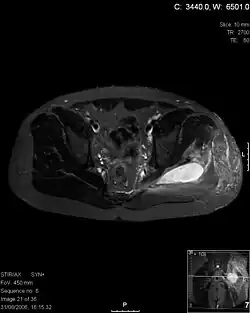

Axial T1 weighted fat suppressed post IV gadolinium contrast enhanced MRI image showing a mutliloculated bacterial abscess in the left gluteal muscle which grew Staphylococcus aureus (methicillin sensitive) thought to be due to tropical pyomyositis.

Coronal fat suppressed post contrast image showing a multiloculated bacterial abscess in the left gluteus minimus muscle due to tropical pyomyositis.